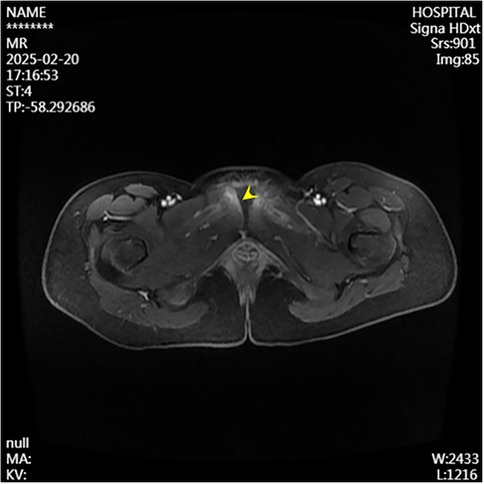

A 13-year-old female presented to the Department of Pediatrics at Dongguan Maternal and Child Health Hospital with a 10-day history of intermittent fever and pain in the pubic symphysis region. The patient denied a history of pelvic surgery, local trauma, or strenuous exercise. Her past medical and family histories were unremarkable. Between February 10 and 18, 2025, she was hospitalized at an external institution due to pubic symphysis pain, restricted lower limb mobility, and high fever. Blood cultures identified the presence of methicillin-resistant Staphylococcus aureus (MRSA) and she was treated initially with cephalosporins and penicillins which resolved the fever but only partially alleviated the pubic pain. Upon transfer to our hospital, physical examination revealed stable vital signs, no fever, localized tenderness and swelling over the pubic symphysis without erythema or fluctuance, bilateral restricted hip motion (aggravated by adduction and abduction), and an antalgic gait. The laboratory findings included a white blood cell count of 6.08 × 109/L (neutrophils: 64.0%), procalcitonin <0.1 ng/ml, and an erythrocyte sedimentation rate (ESR) of 80 mm/h. Blood cultures confirmed the presence of MRSA. Although intravenous antibiotics had resolved the fever, pubic pain and mobility limitations persisted, particularly with limited hip mobility, notably painful external rotation and adduction, where external rotation was less than 15 degrees and adduction was less than 10 degrees. Consultation with orthopedic specialists led to the suspicion of pubic symphysis infection, prompting an MRI examination. The imaging revealed infection of the pubic symphysis with bilateral osteomyelitis and a small abscess in the posteroinferior muscle layer (Figures 1, 2). Based on these clinical manifestations, laboratory results, and imaging findings, the diagnosis was confirmed as pubic symphysis infection with bilateral osteomyelitis and abscess formation.

Figure 2. Preoperative MRI shows infection at the pubic symphysis.

Infection of the pubic symphysis is a rare but serious condition, with early symptoms often being nonspecific and easily overlooked. Patients typically present with pain in the pubic symphysis region, which worsens with movement of the hip joint, restricting mobility and leading to limping. However, these clinical manifestations lack specificity and can be easily confused with other postpartum or postoperative pelvic conditions, such as pubic symphysis diastasis, non-infectious osteitis pubis, pubic symphysis injury, and pubovesical fistula. Additionally, especially in the early stages of the disease, significant bone destruction may not be visible on imaging examinations, further complicating diagnosis. MRI is the imaging modality of choice for diagnosing pubic symphysis infection. Its high-resolution soft tissue imaging capabilities enable the early detection of inflammatory changes, such as bone marrow edema, widening of joint spaces, and inflammatory infiltration of the surrounding soft tissue. In cases where infection is suspected, microbiological tests (e.g., blood or pus cultures) should be performed to identify the causative pathogens. Early MRI evaluation to distinguish infectious from non-infectious lesions can prevent disease progression, including sequestrum formation, abscess development, fistula formation, bilateral pubic ramus bone destruction, and loss of pelvic stability (11). In the present case, the patient's x-ray examination was unremarkable, whereas MRI revealed the presence of bilateral pubic osteomyelitis and an abscess in the posterior muscle layer of the pubic symphysis, further supporting the anatomical basis for the spread of infection in this region. Therefore, in high-risk patients, such as those with fever, and significantly elevated CRP levels and ESR, MRI should be performed even if initial x-ray findings appear normal to avoid misdiagnosis and delayed treatment. In terms of pathogen classification, pubic symphysis infections can be categorized into three types, namely, non-specific (e.g., Staphylococcus aureus), specific (e.g., Mycobacterium tuberculosis), and mixed bacterial infections. Mycobacterium tuberculosis is the most common pathogen responsible for specific bacterial infections and diagnosis is based on its isolation from pus or biopsy tissue. The primary treatment consists of anti-tubercular therapy, with surgical intervention considered in cases of extensive sequestrum formation, fistula development, and failure of conservative management, with generally favorable outcomes (12). Non-specific bacterial infections show similar presentations to non-infectious osteitis pubis, with the key distinguishing feature being an acute onset with fever. Common pathogens include Staphylococcus aureus, Pseudomonas aeruginosa, Escherichia coli, Salmonella species, and anaerobes. However, standardized diagnostic and treatment guidelines for these infections are lacking (13). The primary treatment approach involves pathogen-specific antibiotic therapy, with surgical intervention considered in selected cases. However, there is no consensus on the optimal timing for surgery, and the surgical techniques used vary widely. Common surgical approaches include thorough debridement, local placement of antibiotic beads, holmium laser debridement, or fixation of the pubic symphysis in refractory cases (1417).